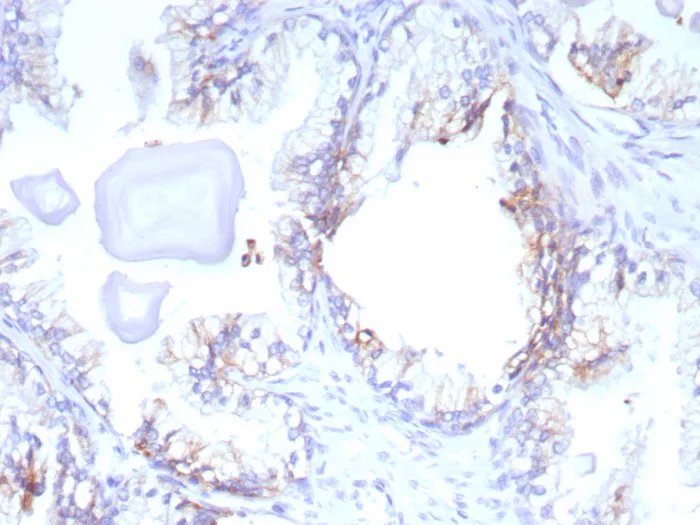

Formalin-fixed, paraffin-embedded human prostate cancer stained with ABCC4 Mouse Monoclonal Antibody (ABCC4/9179). HIER: Tris/EDTA, pH9.0, 45min. 2°C: HRP-polymer, 30min. DAB, 5min.

Formalin-fixed, paraffin-embedded human prostate cancer stained with ABCC4 Mouse Monoclonal Antibody (ABCC4/9019). Inset: PBS instead of primary antibody; secondary only negative control.